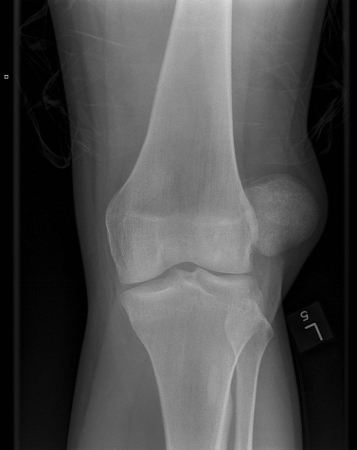

Radiografia do joelho esquerdo demonstrando luxação lateral da patela

Yerimah G, et al. BMJ Case Rep. 2013 May 2:2013:bcr2013009832; usado com permissão